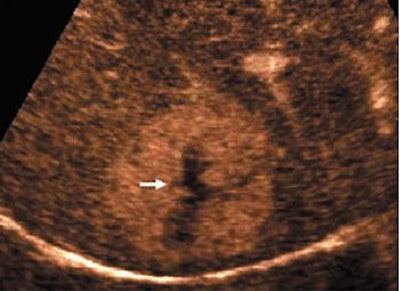

| Transverse contrast-enhanced US scans obtained in contrast-specific mode with pure harmonic detection in 45-year-old woman show typical spoke wheel-shaped contrast-enhancement pattern of focal nodular hyperplasia after microbubble contrast agent injection. Above, central spoke wheel-shaped contrast enhancement (arrow) is evident 15 seconds after the injection (arterial phase). Middle, contrast enhancement (arrow) is diffuse and homogeneous 25 seconds after the injection (arterial phase). Below, contrast enhancement is hyperechoic 105 seconds after the injection, with a central hypoechoic region that corresponds to the central scar (arrow) that is evident during the late phase. |

| Quaia E, Calliada F, Bertolotto M, et al, "Characterization of Focal Liver Lesions with Contrast-specific US Modes and a Sulfur Hexafluoride-filled Microbubble Contrast Agent: Diagnostic Performance and Confidence," Radiology 2004;232:420-430, figure 8a-c. |